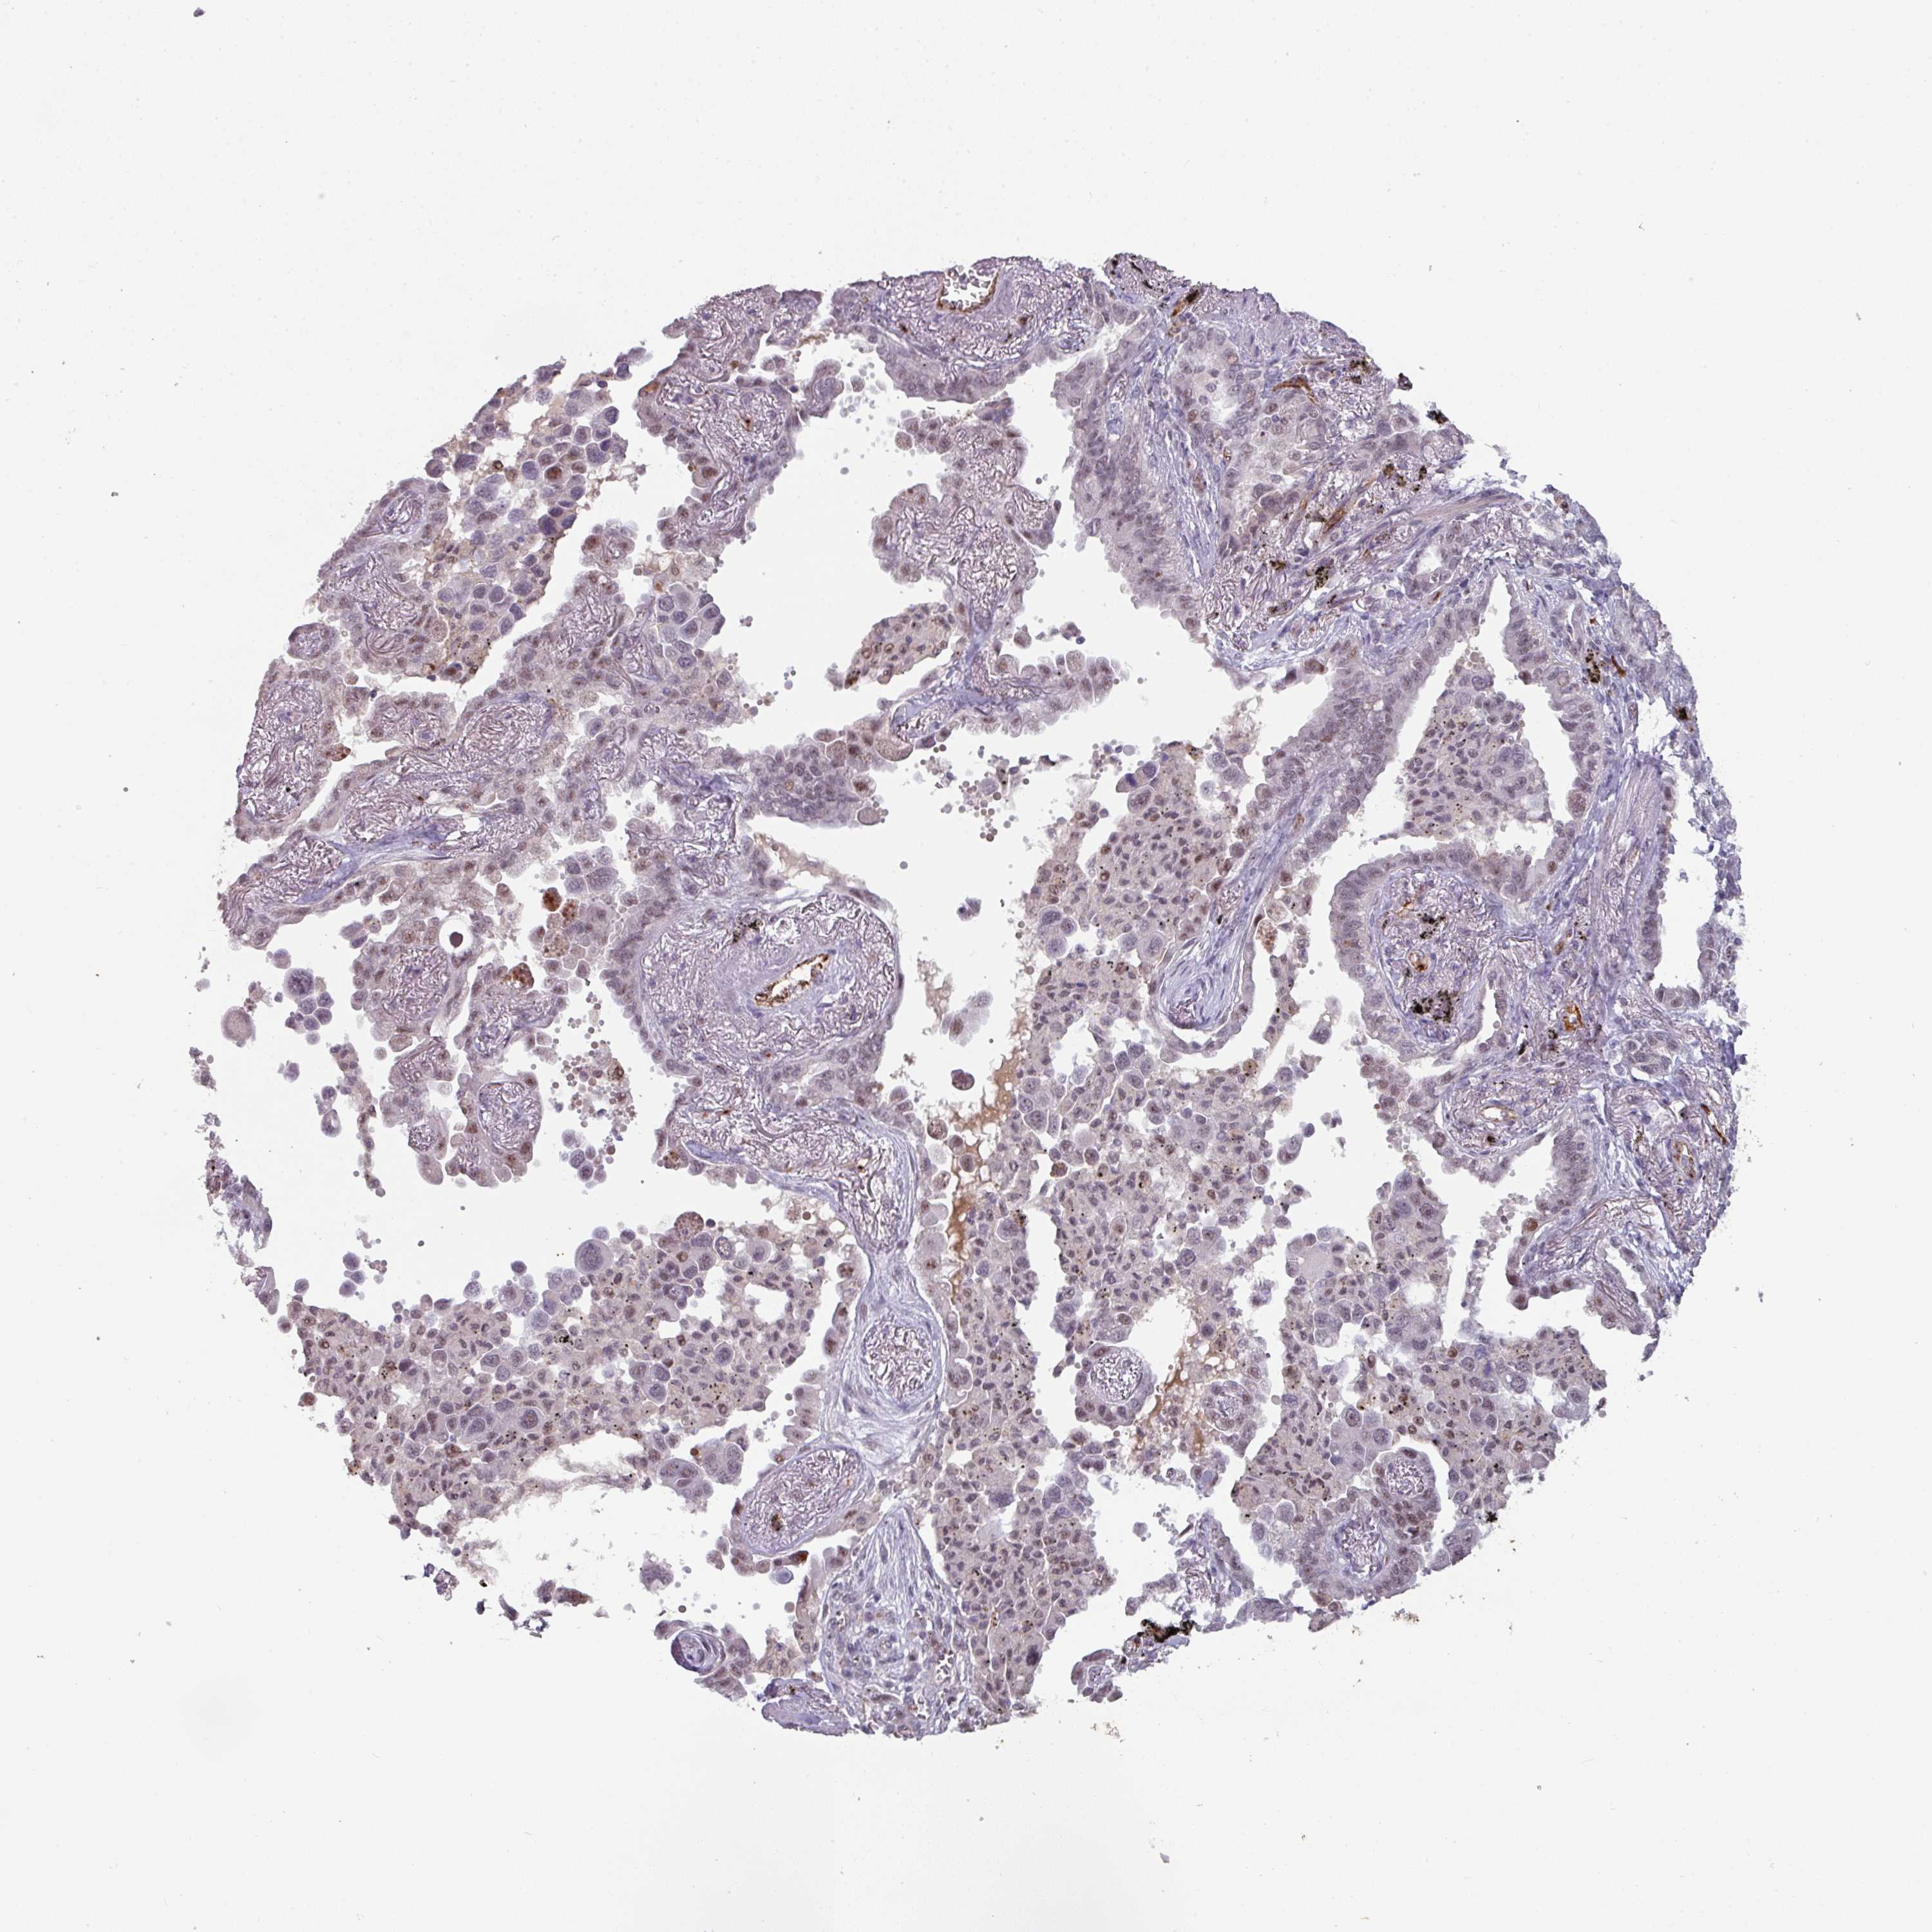

LUNG ADENOCARCINOMA (VALIDATION) - Interactive survival scatter ploti

The Survival Scatter plot shows the clinical status (i.e. dead or alive) for all individuals in the patient cohort, based on the same data that underlies the corresponding Kaplan-Meier plots. Patients that are alive at last time for follow-up are shown in blue and patients who have died during the study are shown in red.

The x-axis shows the expression levels (FPKM) of the investigated gene in the tumor tissue at the time of diagnosis. The y-axis shows the follow-up time after diagnosis (years). Both axes are complimented with kernel density curves demonstrating the data density over the axes. The top density plot shows the expression levels (FPKM) distribution among dead (red) and alive patients (blue). The right density plot shows the data density of the survived years of dead patients with high and low expression levels respectively, stratified using the cutoff indicated by the vertical dashed line through the Survival Scatter plot. This cutoff is automatically defined based on the FPKM cutoff that minimizes the p-score. The cutoff can be changed by dragging the vertical line or by entering a cutoff value in the square labeled "Current cut-off".

Under the Survival Scatter plot the p-score landscape (black curve; left axis) is shown together with dead median separation (red curve; right axis). Dead median separation is the difference in median mRNA expression between patients who have died with high and low expression, respectively. It is calculated as follows: median FPKM expression of dead patients with high expression - median FPKM expression of dead patients with low expression. This is intended to aid the user in visually exploring custom cutoffs and the associated p-scores and dead median separation.

Individual patient data is displayed and can be filtered by clicking on one or more of the category buttons on the top of the page. Categories describing expression level and patient information include: high, low, alive, dead, female, male and tumor stages. The scale of the x-axis can be toggled between linear and log-scale by clicking on the "x log" button. Mouse-over function shows TCGA ID, patient information and mRNA expression (FPKM) for each patient.

& Survival analysisi

Kaplan-Meier plots summarize results from analysis of correlation between mRNA expression level and patient survival. Patients were divided based on level of expression into one of the two groups "low" (under cut off) or "high" (over cut off). X-axis shows time for survival (years) and y-axis shows the probability of survival, where 1.0 corresponds to 100 percent.

SIDT2 is not prognostic in Lung Adenocarcinoma (validation)

Best expression cut offi

: 27.12

P scorei

N/A

TCGA RNA samplesi

RNA-seq data is reported as average FPKM (number Fragments Per Kilobase of exon per Million reads), generated by the The Cancer Genome Atlas (TCGA) .

Normal distribution across the dataset is visualized with box plots, shown as median and 25th and 75th percentiles. Points are displayed as outliers if they are above or below 1.5 times the interquartile range. FPKM values of the individual samples are presented next to the box plot.

Average pTPM 24.7

Number of samples 105